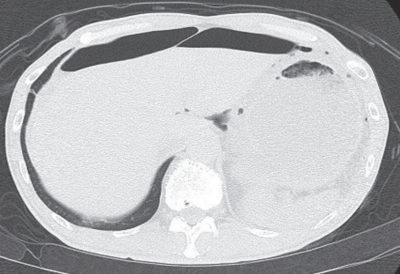

血液所見:赤血球 488万、Hb 14.8g/dL、Ht 44%、白血球12,200、血小板33万。血液生化学所見:総蛋白 6.1 g/dL、アルブミン 3.1 g/dL、総ビリルビン 0.2 mg/dL、AST 18 U/L、ALT 19 U/L、LD 135 U/L(基準120~245)、尿素窒素 10 mg/dL、クレアチニン 0.7 mg/dL。CRP 1.7 mg/dL。腹部単純CTの軟部条件と肺野条件を別に示す。